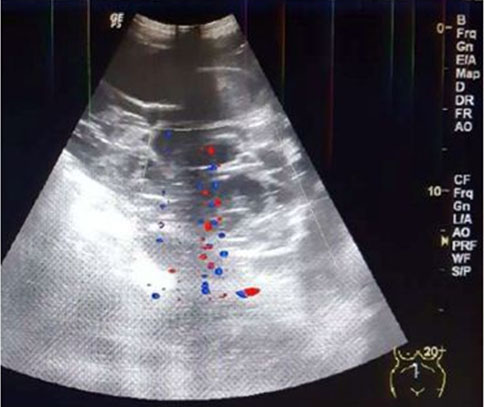

Obstetrical US at 22 weeks and 5 days gestational age for fetal survey revealed a single male fetus in vertex position with a posterior placenta free of the cervical os. Growth, fetal survey, and a biophysical profile were normal. An anterior mural based multi-cystic lenticular shaped uterine mass measuring 11.8 cm long × 4.2 cm AP × 12.8 cm W was completely separate from the posterior placenta in the gestational sac of the live fetus. Color Doppler evaluation showed prominent vascularity within the mass (Figure 1A and Figure 1B).

Figure 1: Transabdominal US of concomitant complete molar pregnancy anteriorly with live fetal twin. US shows: (A) Anterior mass with multiple tiny cysts (white arrow) and posterior placenta noted (red arrow) that abuts the gestational sac. (B) Molar mass has prominent blood flow on color flow Doppler imaging (small arrows).